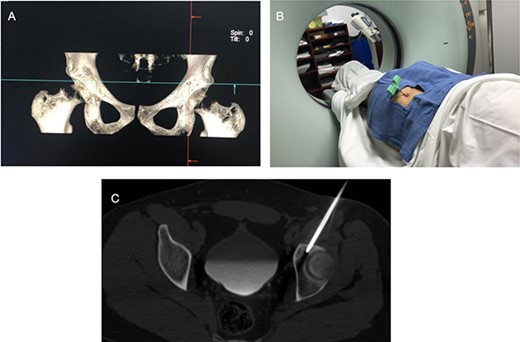

The procedure was made with general anesthesia and in supine position. A 1-cm incision was made for an anterior approach over the hip joint. Careful blunt dissection was done. Percutaneous technique was used with the guidance of a 64 slice Somatom sensation CT scanner (Siemens AG Munich, Germany) with interval cuts of 2 mm to locate the OO. Intravenous contrast was administered to identify the vascular structures at risk (Fig. 3). A 13G × 100 mm bone marrow biopsy needle was used. Image guidance was performed by a senior radiologist (ES). Once the OO was located, accurate insertion of the needle was monitored, and drilling was done manually to help precision in depth (Fig. 4). Multiple bone fragments were obtained and sampled. Immediate image verification showed a space missing the nidus OO. To avoid leaving remnant nidus, curettage was added on the edges and the deep margin of the tumor. Bone samples were sent to histological evaluation and OO diagnosis was confirmed. Wound pain management was administered for 2 weeks and night symptoms disappeared immediately. Complete relief was achieved 3 weeks later. A 12-month follow-up post treatment reported no recurrence of pain and no complications with wound management. ROM and athletic activities are painless. No soft tissue complications were reported.

CT with intravenous contrast showing the femoral vessel (yellow arrow) before the procedure to obtain proper approach (red arrow showing the OO).

CT showing the precise site for needle insertion (A), CT control of the needle insertion (B,C).